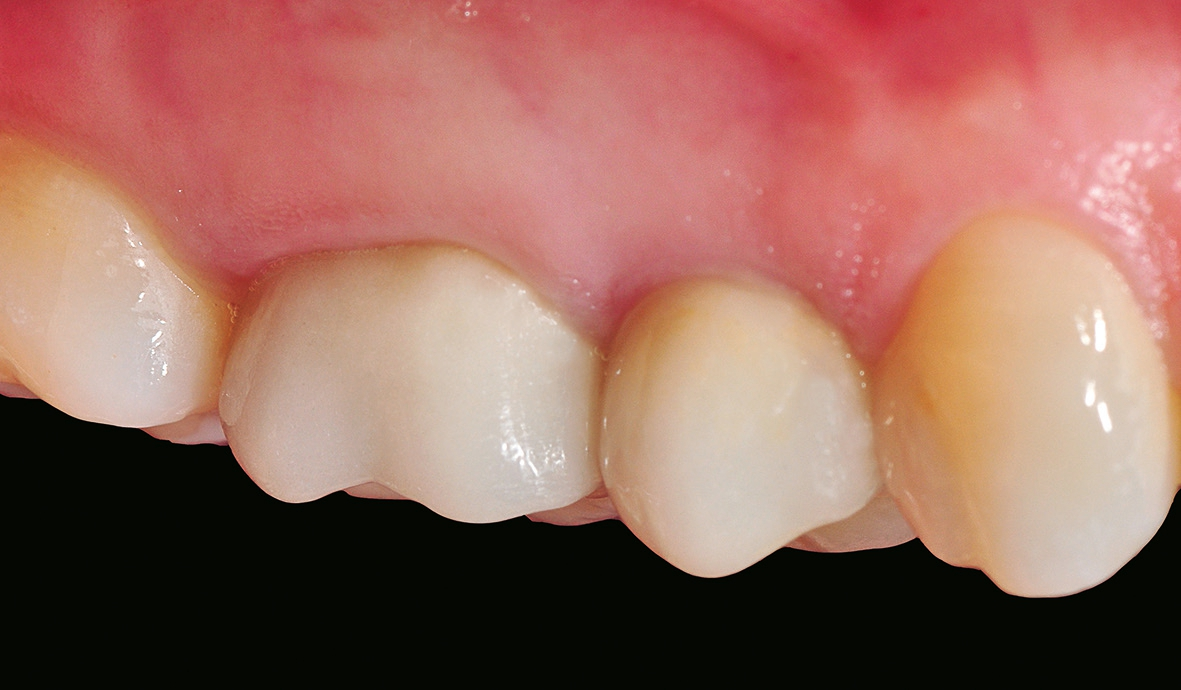

Nach einer komplikationsfreien Einheilzeit von vier Monaten konnte mit der Herstellung des definitiven Zahnersatzes begonnen werden. Hier entschied man sich konsequent für monolithische Kronen aus Lithiumdisilikat, um das Chippingrisiko so gering wie möglich zu halten [12]. Im Zuge der Implantatversorgung wurde nun auch – wie geplant – die metallkeramische Krone an 16 geschlitzt, entfernt und der Stumpf nachpräpariert. Implantatkopf und Zahnstumpf wurden daraufhin zusammen mit A-Silikon analog abgeformt. Für die geschlossene Abformung wurde die Abformkappe (impression.transfer) auf dem Implantatkopf positioniert. Ein deutliches Einrasten signalisierte den lagestabilen Sitz. Für die Modellherstellung rastete das Implantatanalog (lab. replica) ebenso in die integrierte Abformkappe ein. Nach der Herstellung des Meistermodells konnten die beiden Kronen im digitalen Workflow CAD/ CAM-gestützt gefertigt werden. Nach Ausarbeitung, Bemalung und Glasur waren die beiden Kronen für die definitive Zementierung bereit. Die klinische Einprobe der Restaurationen verlief erfolgreich, sodass die Kronen nacheinander mit selbstadhäsivem Befestigungskomposit eingegliedert werden konnten.

Aber auch bei einem nachträglichen Bindegewebstransplantat zur gingivalen Korrektur bietet ein einteiliges, spaltfreies Implantat aus gewebefreundlichem Zirkondioxid womöglich bessere Chancen auf eine zufriedenstellende rote Ästhetik als zweiteilige Titanlösungen. Die Patientin war in diesem Fall mit dem ästhetischen Erscheinungsbild und der Funktionalität ihrer neuen Versorgungen eineinhalb Monate nach der definitiven Eingliederung absolut zufrieden.